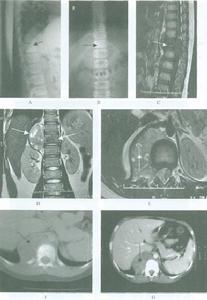

單側關節突關節脫位單側關節突關節脫位X線片示意圖,前後位於顯示脫位頸椎的棘突偏離中央向小關節脫的一側偏移斜位片,可清楚地顯示小關節脫位或“交鎖”徵象。

1.前後位片顯示脫位頸椎的棘突偏離中央,向小關節脫位的一側偏移。

2.側位X線片典型徵象為椎體脫位前移距離為1/3~1/2椎體前後徑。脫位節段上方的關節突顯示雙重影,動力位片時脫位頸椎不能完全復位。

3.斜位片顯示小關節脫位或“交鎖”徵象或關節突關節小的骨折片。

C6/7單側關節突交鎖、C4/5單側關節突交鎖、頸椎X線側位片示:C6/7關節突交鎖,椎頸椎X線側位片示:C4/5單側關節突交體脫位前移距離為1’3椎體前後徑鎖。

C4/5半脫位及C。棘突骨折C4/5半脫位頸椎X線正位片(A)、側位片(B)示:C4/5半脫位。小關節絞鎖。椎間隙變窄;動力位過伸位(c)、過屈位(D)示:脫位狀態下不可復位;頸椎MRl矢狀T2wI像(E)、TlwI像(F)示:C4/5半脫位,椎間盤與後縱韌帶受損。脊髓形態、信號正常。頸椎骨折內固定術後頸椎X線正側位(G)。